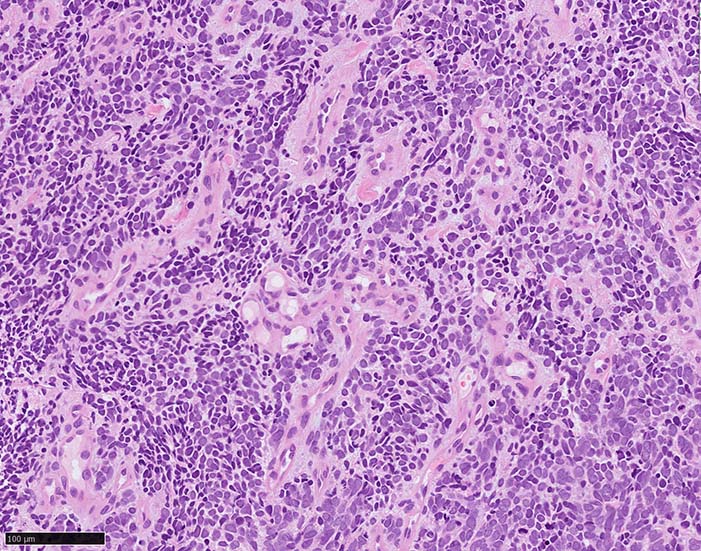

皮膚原発性Merkel細胞癌は 通常真皮を病変首座に増殖し, しばしば脂肪織まで浸潤する.

表皮とは連続性がなくGrenz zoneがみられるのが特徴であるが, 病理所見は多様であり, ときに表皮向性を示す症例やpagetoid patternを呈する症例もある.

典型的な腫瘍細胞は円形, 卵円形の比較的均一な形態で「salt-and-pepper」と称される微細顆粒状クロマチンを有する小型円形核をもつ. MCPyV陽性例が均一な小型円形核を呈する傾向があり, 陰性例では, 核多形性が目立つととする報告がある.

trabecular type, intermediate type, samll cell typeの3パターンの組織型に分類されているがしばしば混在している.

- trabecular typeは円形から多稜形の腫瘍細胞が索状に配列, 3形のなかで腫瘍細胞がもっとも大きく, 円形核と比較的豊富な細胞質をもつ.

- small cell typeは濃いクロマチン, 多形性を示す核をもつN/C比大の小型腫瘍細胞がびまん性に増殖する.

- intermediate typeではtrabecular, samll cell typeの中間の腫瘍細胞サイズを示す. 組織型としてはもっとも多い.

腫瘍内浸潤リンパ球/炎症細胞は多くの症例で認められる. リンパ球の腫瘍内浸潤は予後良好因子と報告されている. 16

血管を間質にしてround cellsが索状に増殖する所見. rossett様配列がある. CK20は特徴的な dot-like patternを示す. クリックで大きな画像が見られます.